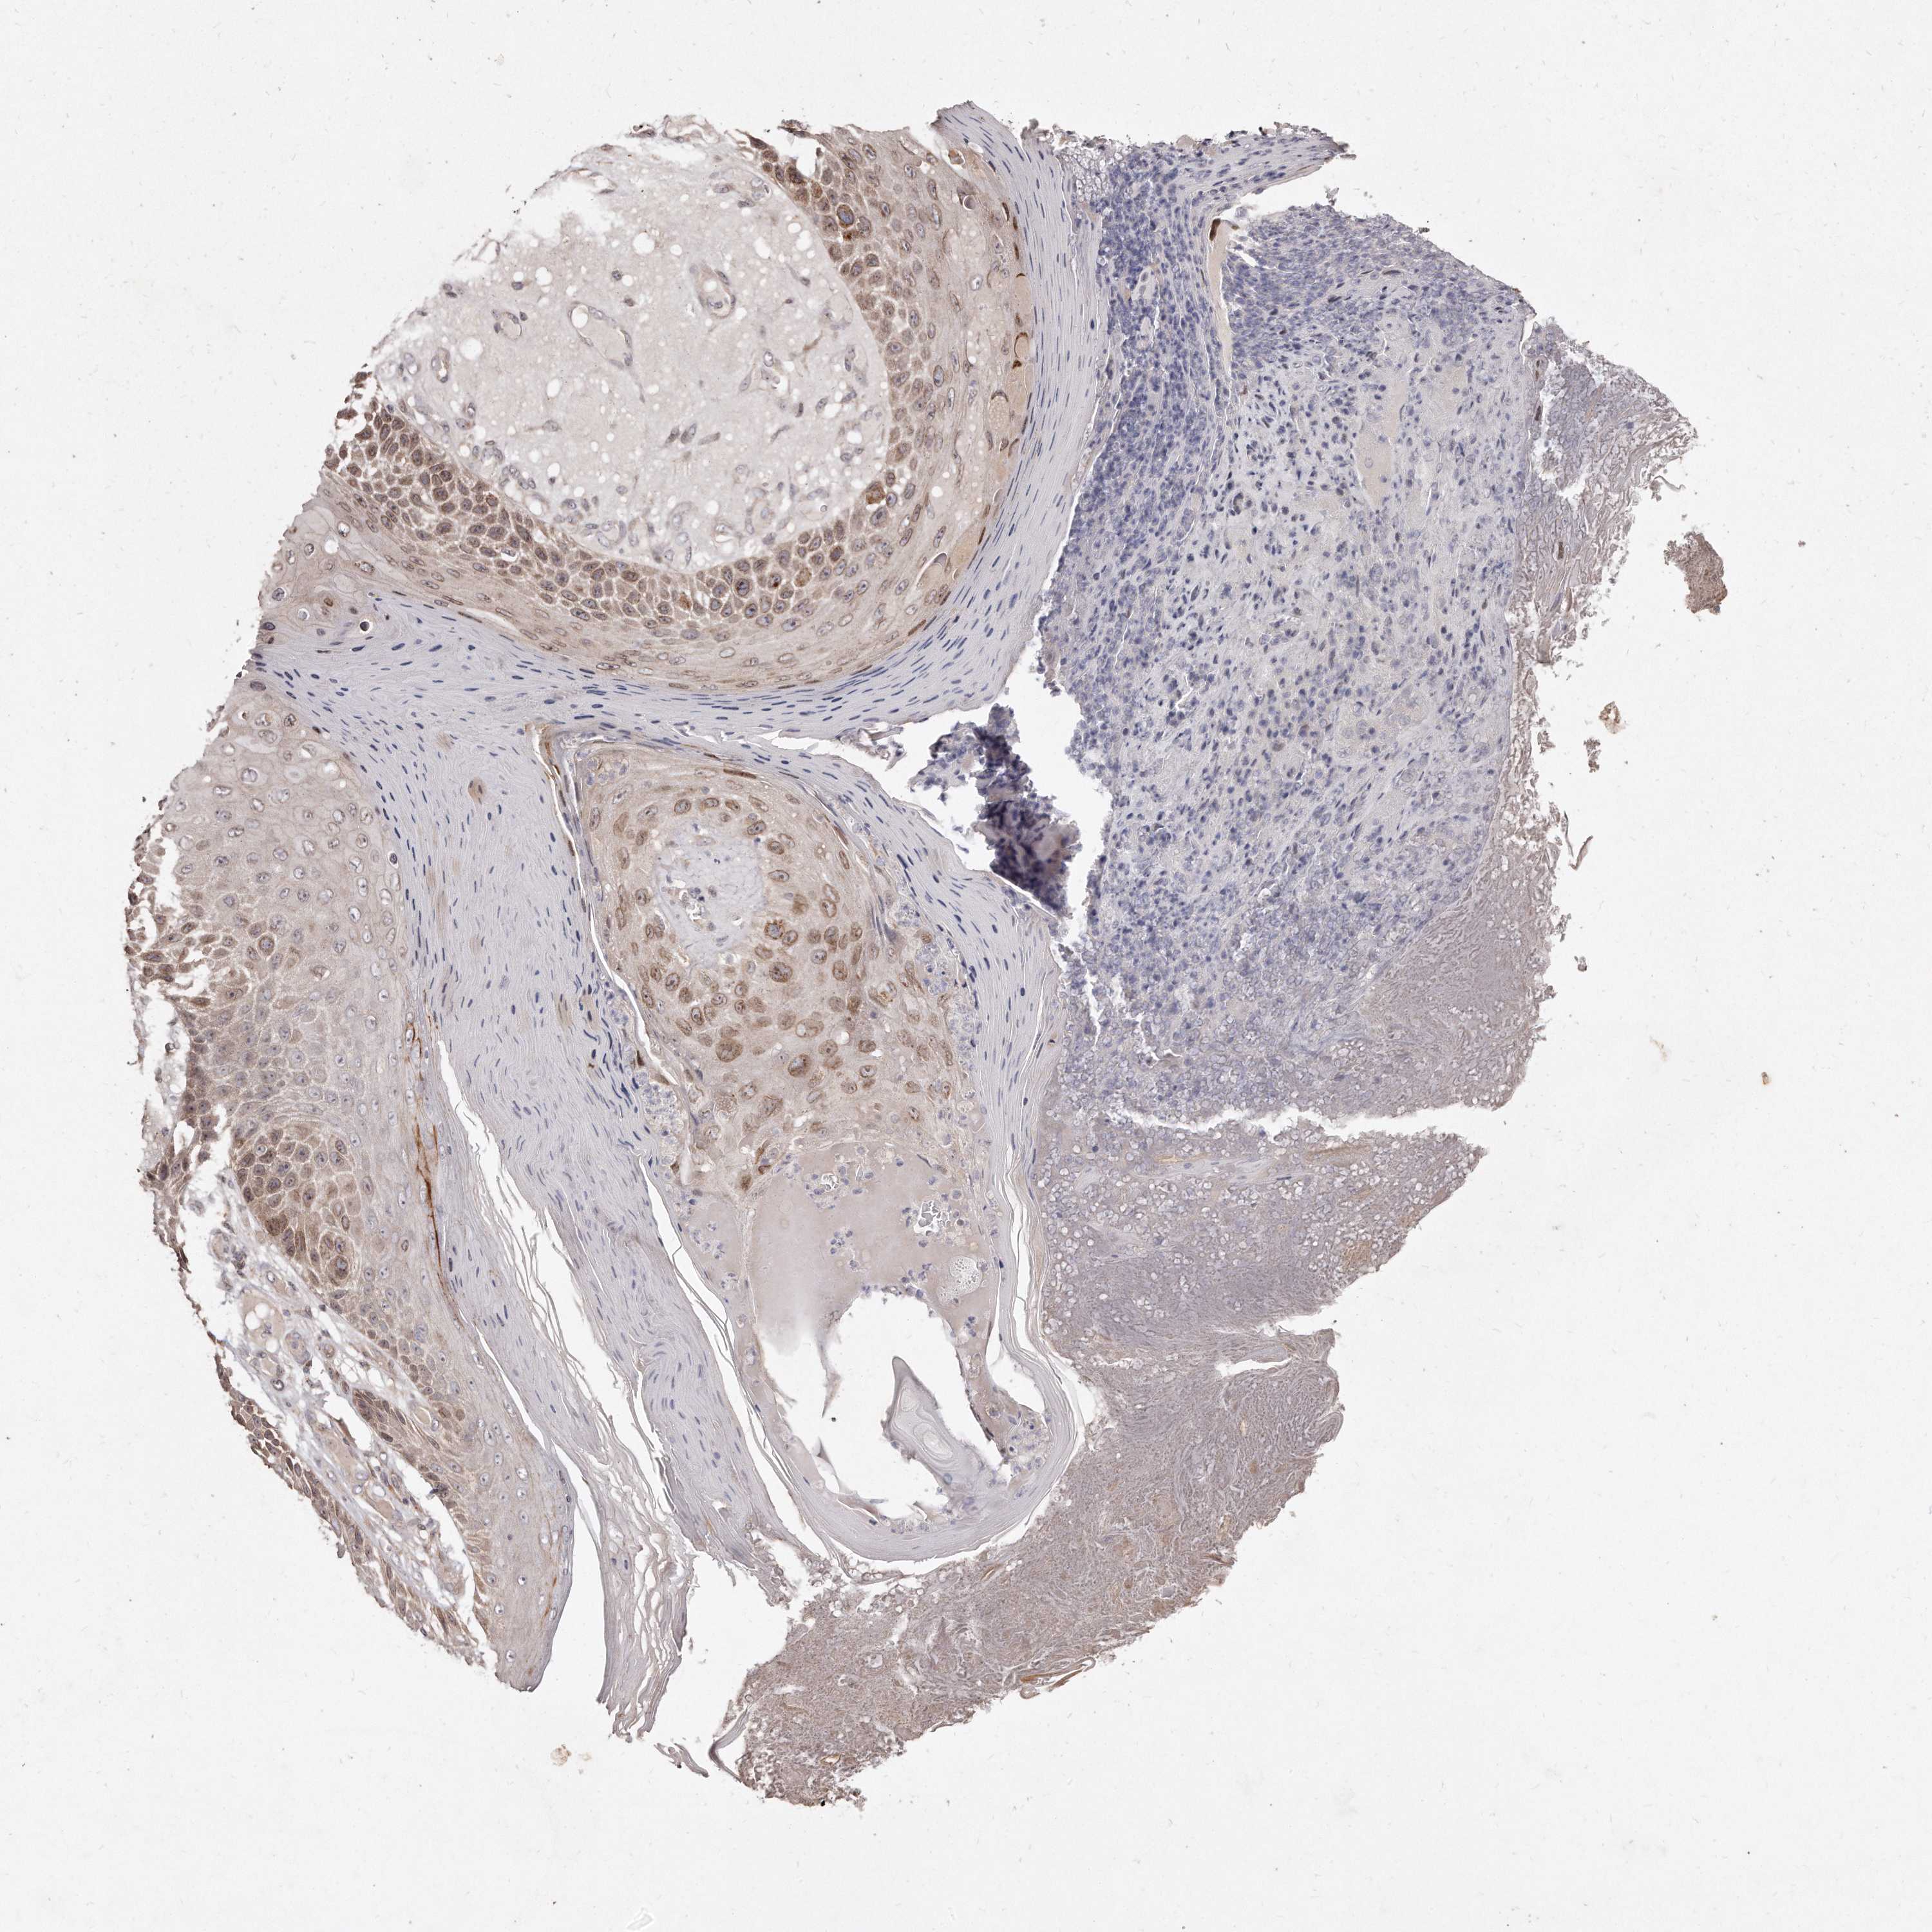

SKIN CANCER - Protein expressioni

A mouse-over function shows sample information and annotation data. Click on an image to view it in a full screen mode. Samples can be filtered based on level of antibody staining by selecting one or several of the following categories: high, medium, low and not detected. The assay and annotation is described here.

Antibody stainingi

Antibody staining in the annotated cell types in the current human tissue is reported as not detected, low, medium, or high, based on conventional immunohistochemistry profiling in selected tissues. This score is based on the combination of the staining intensity and fraction of stained cells.

Each image is clickable and will lead to virtual microscopy that enables deeper exploration of all samples and also displays staining intensity scores, fraction scores and subcellular localization as well as patient and tissue information for each sample.

Antibody HPA027422

Staining

High

Medium

Low

Not detected

Intensity

Strong

Moderate

Weak

Negative

Quantity

>75%

75%-25%

<25%

None

Location

Nuclear

Cytoplasmic/membranous

Cytoplasmic/membranous,nuclear

Basal cell carcinoma